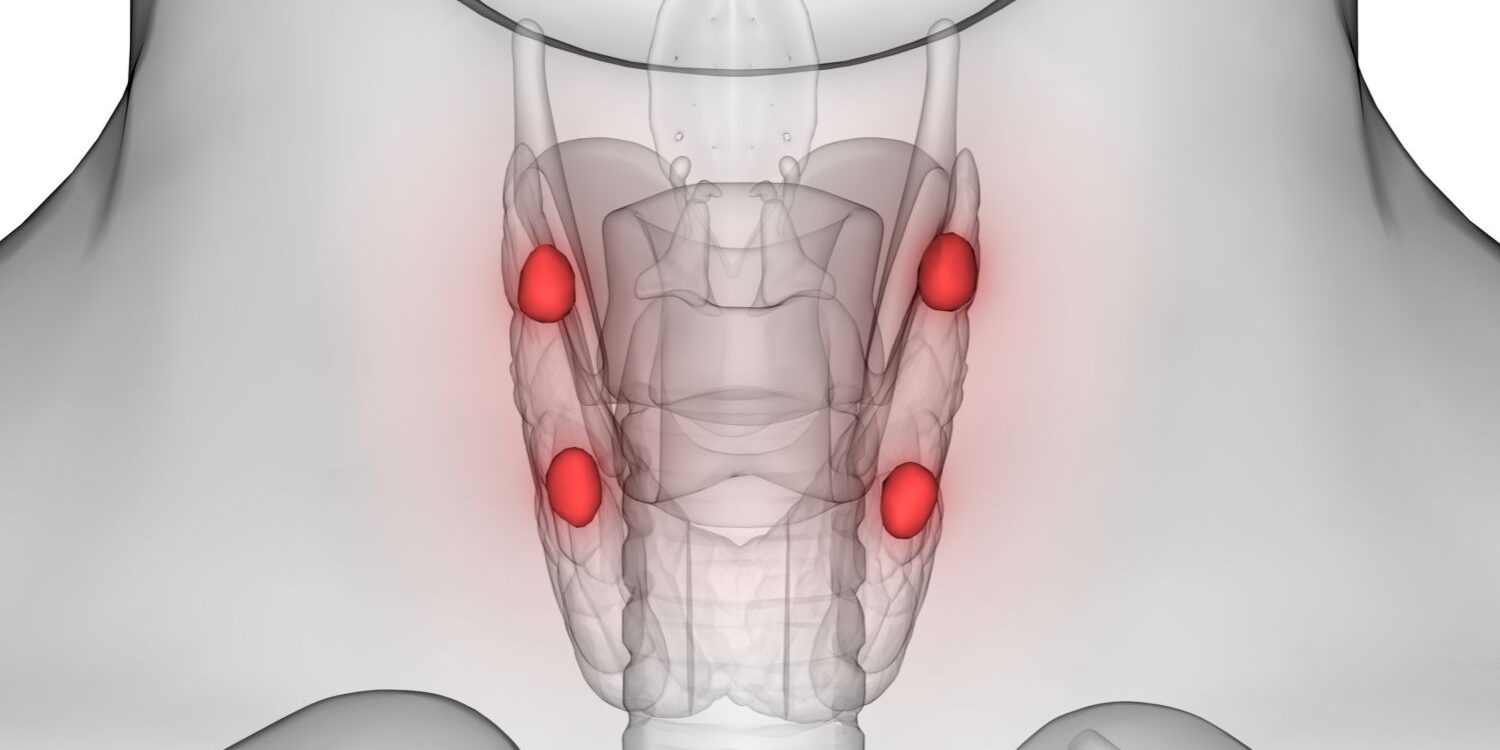

Paratiroid bezleri, boynun ön kısmında tiroid bezinin arka tarafında yer alan, genellikle dört adet küçük ve hayati öneme sahip salgı bezleridir. Bu bezler, vücuttaki kalsiyum dengesini ayarlamakla görevlidir. Paratiroid bezlerinden biri ya da birkaçı zarar gördüğünde, kanda kalsiyum seviyelerinde ciddi bozulmalar meydana gelir.

Paratiroid Bezi Hastalıkları, tiroid bezinin arkasında yer alan ve parathormon (PTH) salgılayan küçük bezlerin fonksiyon bozuklukları sonucu ortaya çıkar. Bu hastalıklar, vücuttaki kalsiyum-fosfor dengesini alt üst edebilir ve kemiklerden böbreklere kadar pek çok sistemi etkileyebilir. Doğru tanı ve zamanında tedavi, ciddi komplikasyonların önlenmesi açısından kritik öneme sahiptir.